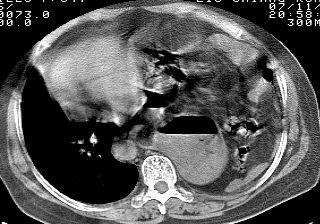

标题: CT10753:女, 64岁 隔疝 [打印本页]

标题: CT10753:女, 64岁 隔疝

女, 64岁 三十年前胸部外伤史, 间断胸闷,

典型左侧膈疝,疝出物为胃和大网膜,纵隔右移

同意左侧膈疝,不过,有过外伤史,左肺有受压征象,同时有胸膜增厚。

典型左侧膈疝,如此严重少见。